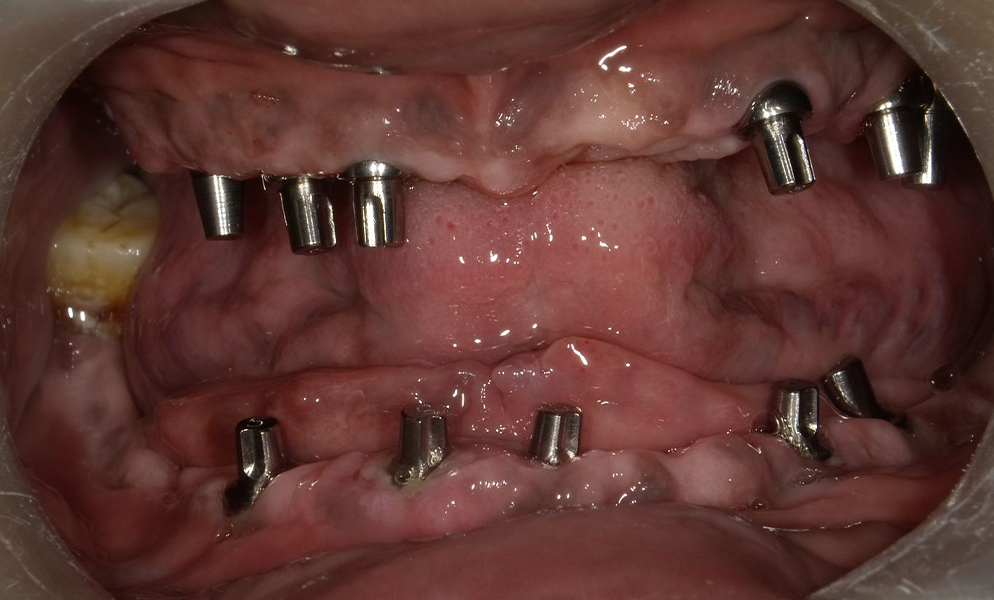

![]() |

| Full-mouth reconstruction with short dental implant (Bicon, USA)-supported prosthesis | |